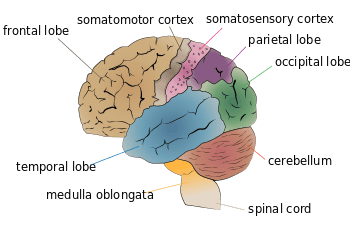

The lateral postcentral gyrus is a prominent structure in the parietal lobe of the human brain. It is the location of the primary somatosensory cortex, the main sensory receptive area for the sense of touch. Like other sensory areas, there is a map of sensory space in this location, called the sensory homunculus.

Structure

The lateral postcentral gyrus is bounded by:

- medial longitudinal fissure medially (to the middle)

- central sulcus rostrally (in front)

- postcentral sulcus caudally (in back)

- lateral sulcus inferiorly (underneath)

Primary cortici, including primary somatosensory cortex (labeled in purple)

Primary cortici, including primary somatosensory cortex (labeled in purple)